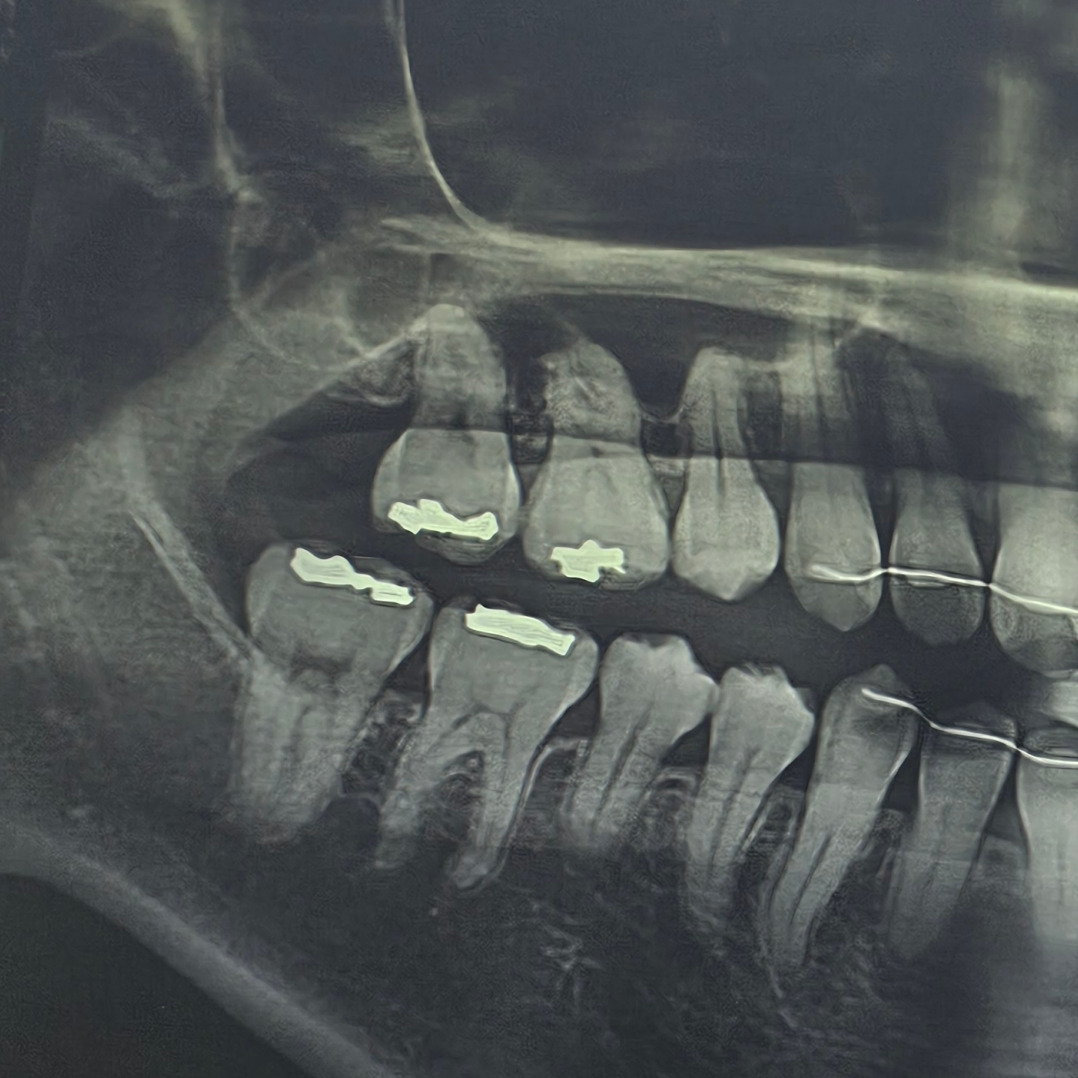

다음 코스는 치과.

정기검진 받을 때가 되어서 벼르고 있었다.

미용실 바로 옆에 치과가 있어서

끝나고 바로 치과로 쏙~.

스케일링도 주기적으로 받고 있는데

드디어 때가 되었다.

결과는..

두둥

아말감 떨어져서 새로 본떴다.

마취 주사가 제일 아팠다.

토요일에 남편과 카페 데이트 가기로 했는데

치과부터 와서 치료받아야 한다.

그래도 명절 연휴 전에 깔끔하게 끝내놓으면 돼서

다행이고,

혹여나 임신 가능성 있기 전에

치과 치료도 끝내 놓을 수 있어서 다행이다.

스케일링까지 받고 나니

뒤늦게 몸이 피곤하다.

치과 치료는 항상 긴장하게 되어서

몸이 힘들어지는 건 변함없다.